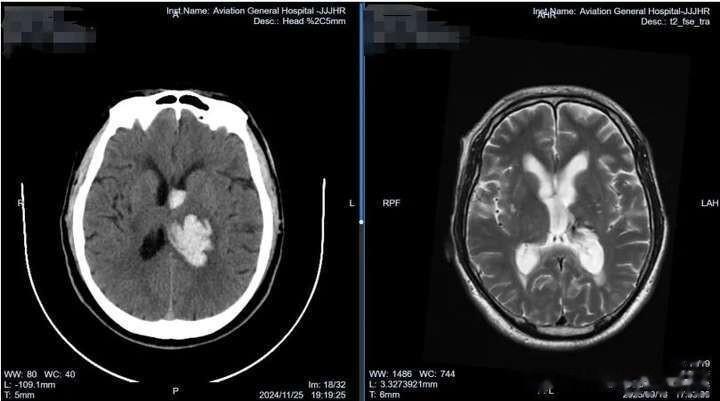

患者田某,于2024年11月25日下午4时无明显诱因突然摔倒在地,右侧肢体活动不利,小便失禁。120急救车送往北京航空总医院后,头颅CT检查提示:左侧丘脑出血,破入脑室。

第一关是出血关:发生在发病前三天。此阶段主要目标是阻止出血量继续增加,避免病情进一步恶化。田某入院后,肖庆主任团队急诊行脑室腹壁长程外引流,术后持续引流置换脑脊液,并给予尿激酶鞘内注射。这一微创干预迅速控制了颅内出血情况,避免了血肿扩大。同时,团队针对发病原因给予预防感染、止血、降压等对症治疗,严密监测血压变化,采用三种降压药物联合方案,确保血压稳定。